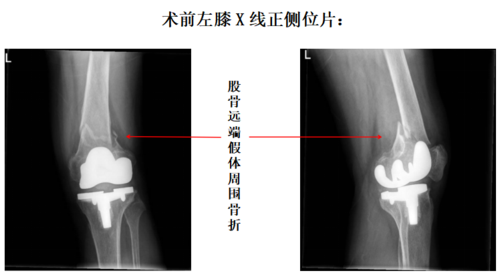

全功能智慧医院今年62岁的丁大爷,3年前因“左膝骨性关节炎”接受了“左膝全膝关节置换手术”,术后丁大爷恢复良好,日常生活不受影响。4小时前,丁大爷不幸遭遇车祸,伤后即感左膝部剧烈疼痛、不敢活动,并迅速出现肿胀,就诊于我院急诊外科,进行了X线检查后发现,丁大爷发生了左膝关节置换术后股骨假体周围骨折。急诊外科紧急邀请关节外一科李磊副主任医师进行会诊,李主任进行了查体并仔细阅片后,建议患者入院接受手术治疗。

入院后完善膝关节CT等相关辅助检查,进一步明确骨折的类型,排除手术禁忌后,李磊主任团队为丁大爷做了“左膝关节置换术后股骨假体周围骨折切开复位内固定手术”。术中探查见膝关节股骨假体稳定,无明显假体松动,股骨远端与股骨假体交界处骨折,为短斜形,呈短缩移位。给予骨折牵引复位后,分别与膝关节内侧、外侧各放置一枚钢板固定。术后7天,丁大爷顺利出院,目前正在积极康复中。

如何治疗股骨假体周围骨折? 如何对假体周围骨折进行治疗,是一个重要的问题。据李磊副主任医师介绍,假体周围骨折在高危人群中的发生率和死亡率较高,尤其是高龄老人。针对膝关节置换术后股骨假体周围骨折,最常用的分型系统是Rorabeck和Taylor分型,该分型系统同时考虑骨折的移位程度和假体稳定性。一般情况下,I型骨折可行保守治疗,II型骨折应采用内固定治疗,而III型骨折则需要进行假体翻修手术。本例患者骨折线位于股骨远端、股骨假体的上方,骨折端移位明显,同时膝关节股骨假体稳定,骨折分型为II型。因此,我们为丁大爷选择了内固定手术治疗。